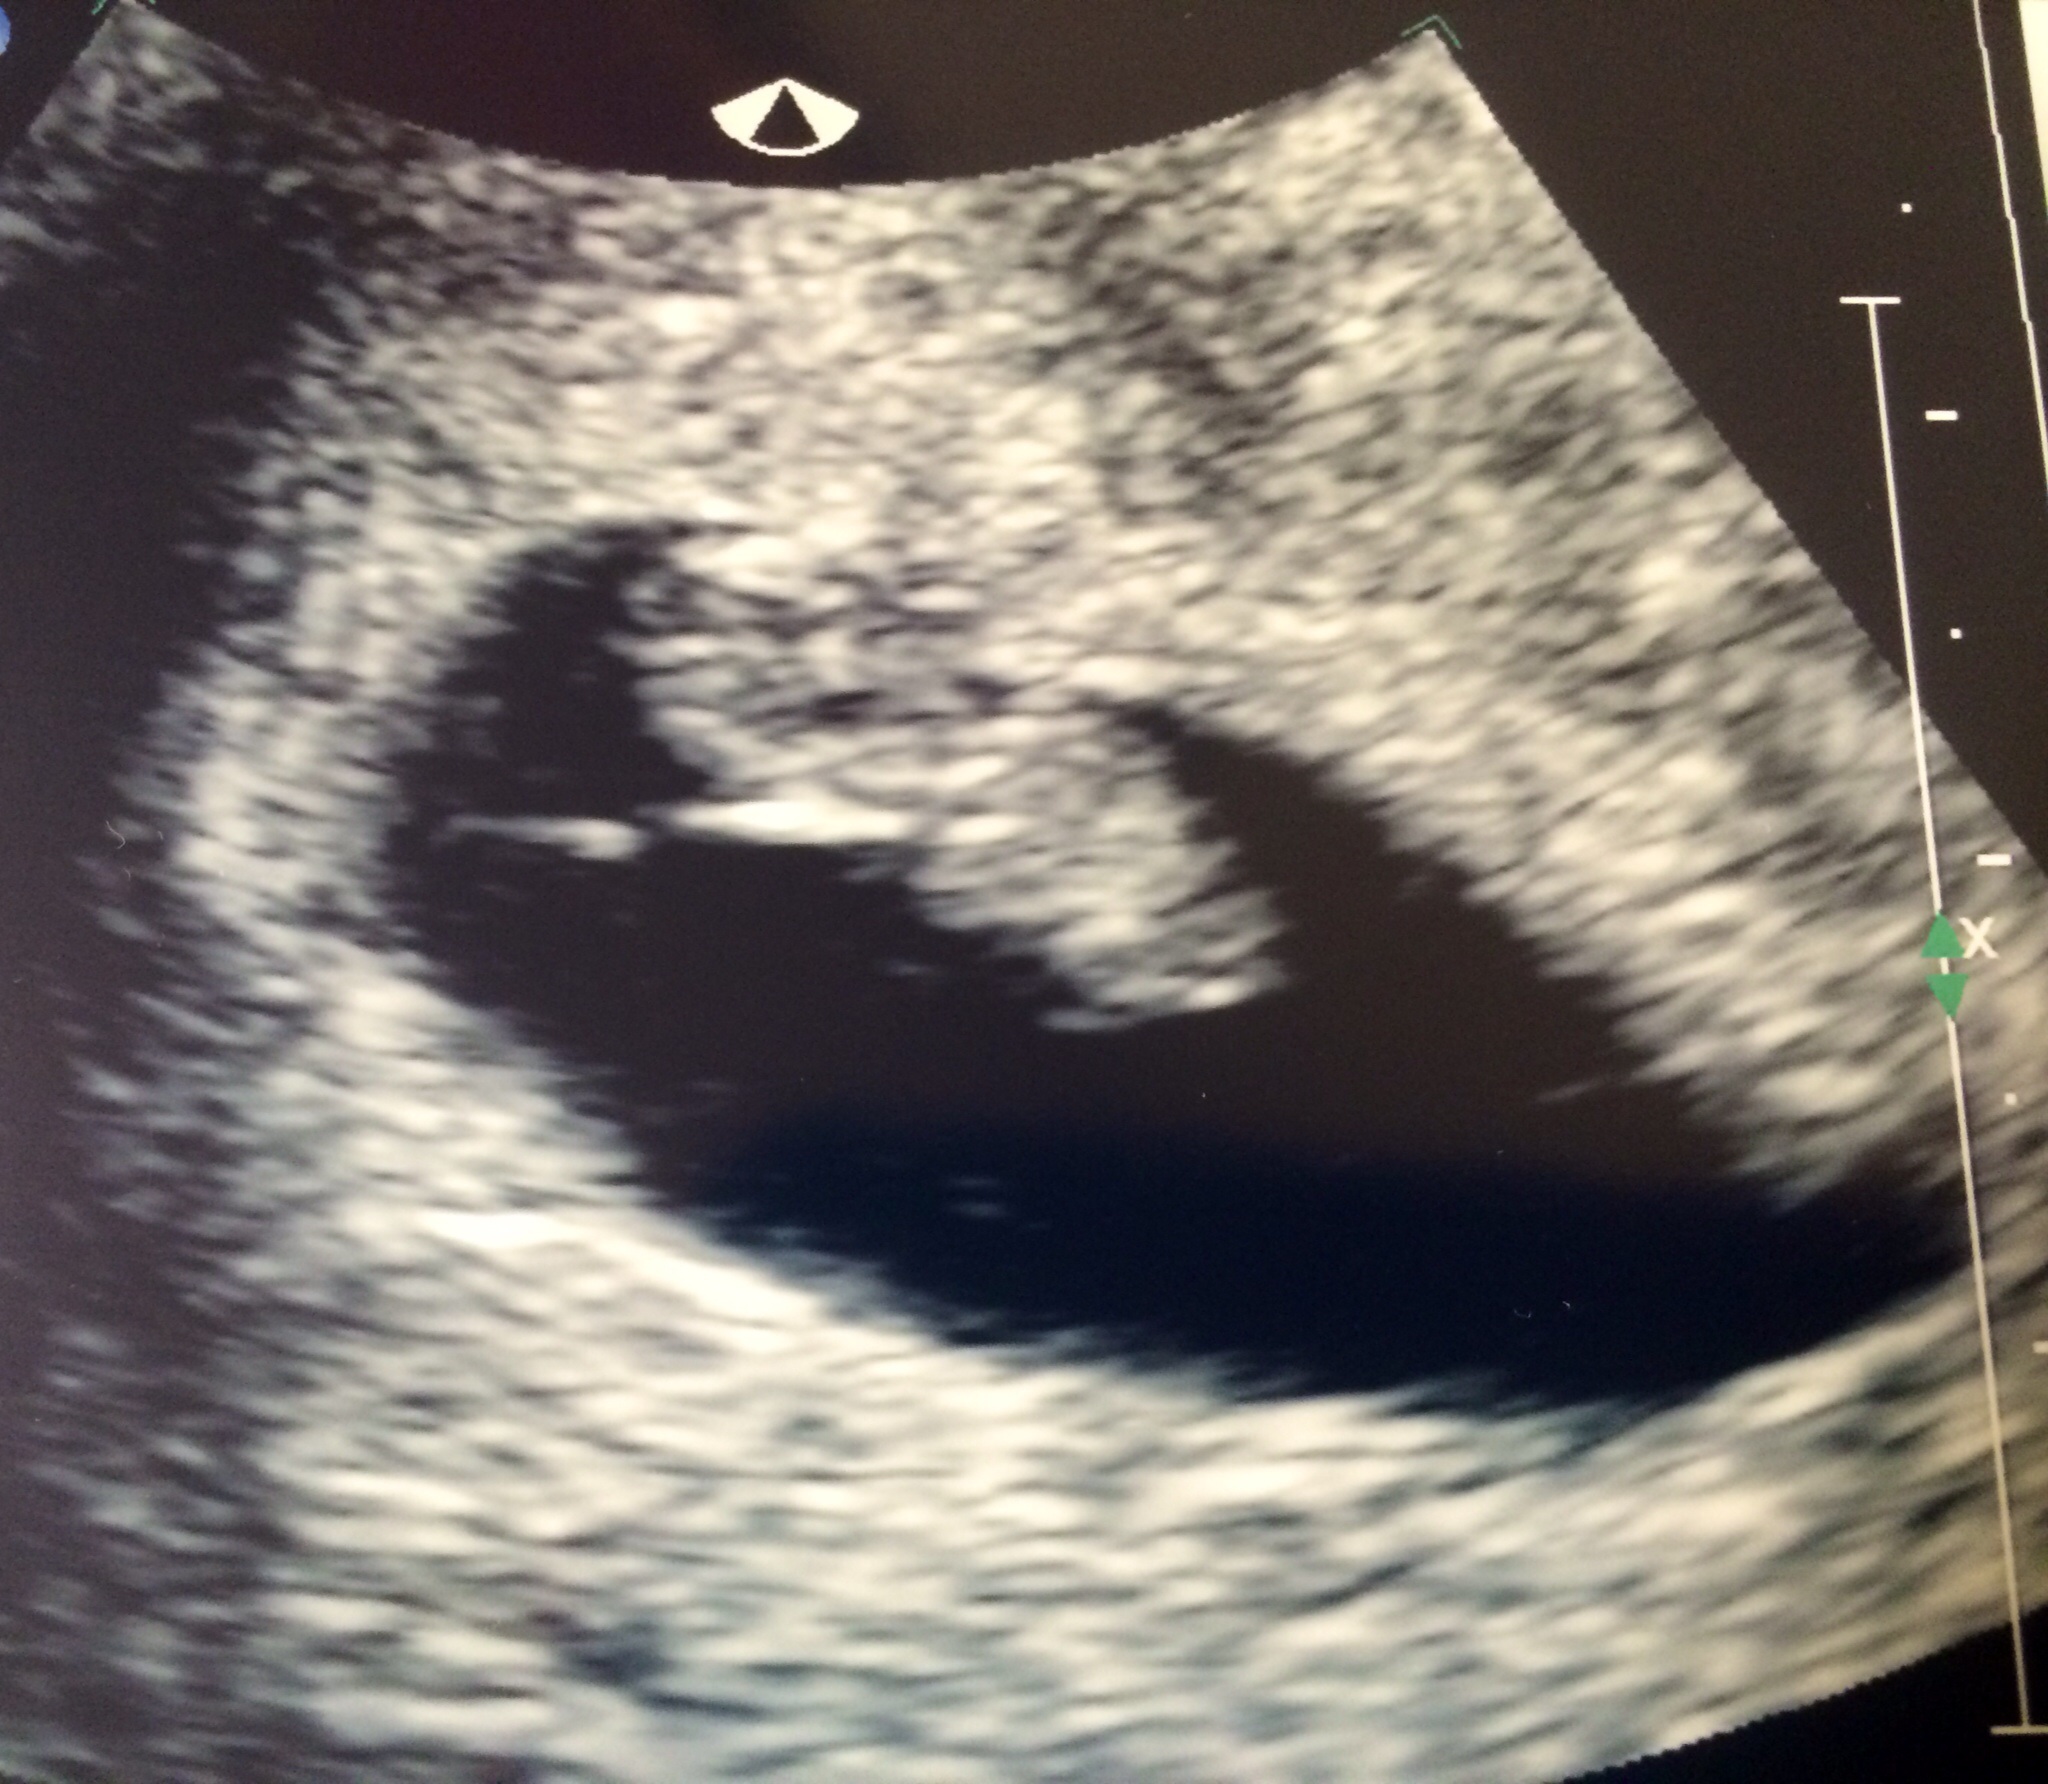

Yesterday I went in for the 12 week scan, including NT screening. Here's the little one. They also showed me in 3-d & the baby was holding onto the placenta.